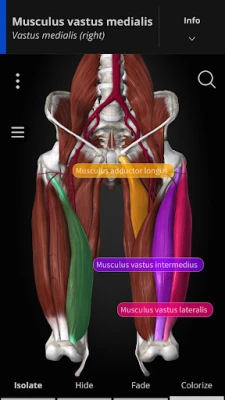

Using our cutting-edge 3D model, which is one of the most detailed in the world, ANATOMYKA allows you to get up close with human anatomy in all its breathtaking complexity on more than 13,000 anatomical structures with more than 500 pages of medical descriptions. Now in English, Spanish, Italian, Polish, Russian, Czech, Slovak and Hungarian localization.

Color-coded organs allow users to view high-resolution anatomical structures supplemented by informative descriptions from a comprehensive textbook ‘Memorix Anatomy’. These are arranged into a proper anatomical hierarchy, meaning learning is structured and easy to understand.

LABELS

Create labels and pin them to different parts of the body. Labels automatically highlight the name and color of the organ and are great for creating anatomical posters.

- User-friendly interface: Zoom, rotate, scale, colorize, isolate, select, hide, and fade all anatomical structures

Color-coded organs allow users to view high-resolution anatomical structures supplemented by informative descriptions from a comprehensive textbook ‘Memorix Anatomy’. These are arranged into a proper anatomical hierarchy, meaning learning is structured and easy to understand.

LABELS

Create labels and pin them to different parts of the body. Labels automatically highlight the name and color of the organ and are great for creating anatomical posters.

- User-friendly interface: Zoom, rotate, scale, colorize, isolate, select, hide, and fade all anatomical structures